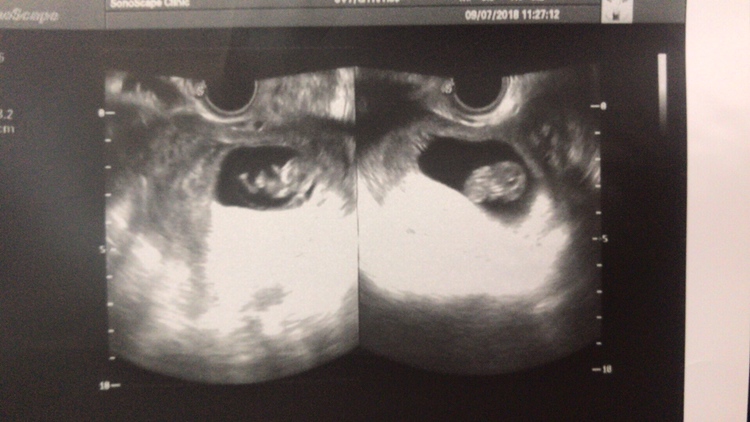

左边nt图是男宝宝?

绿豆娃娃iHuf[帖主]:嗯,左边男宝宝,右边女宝宝